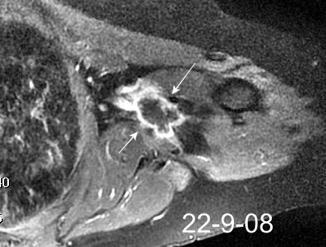

Tumor desmoide derecho. Recidiva.

Tumor maligno. 0,2% de los tumores de mama.

Ocurren en 10% de los implantes de mama.

En los 3 años después del implante.

(Dudas sobre el dato)

Kilmartin C et al. Desmoid Tumor and Implant-Based Breast Reconstruction. Case Rep Oncol. 2023